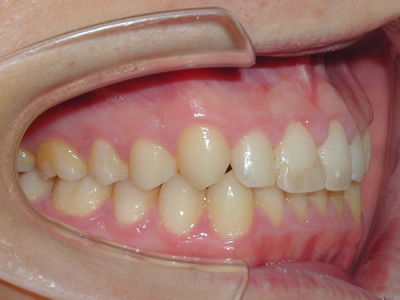

上顎の劣成長 (成長不足) による反対咬合で、上顎は拡大装置と上顎前方牽引装置を併用し前方方向への成長を促して前歯の咬み合わせを改善した後に、上下顎の前歯をマルチブラケット装置で並べました。治療の期間は2年でした。

初診時